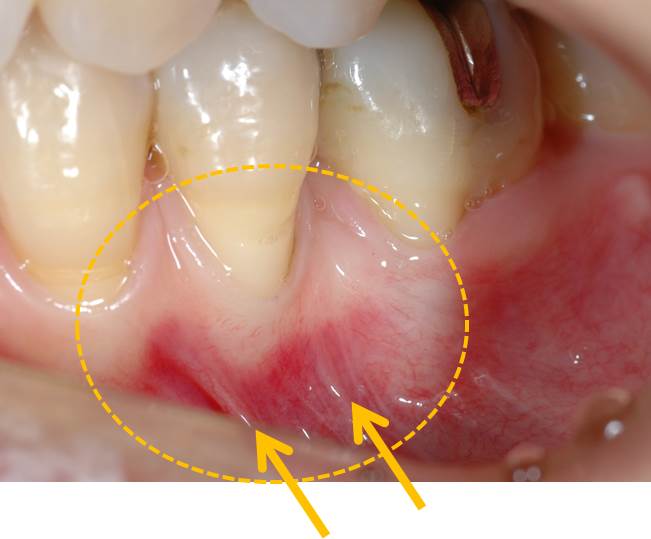

歯科矯正後に「歯がしみる」という主訴で来院されました。いわゆる知覚過敏で虫歯ではありません。歯肉が薄く、動かない歯肉が少ないために歯肉が痩せてしまっています。さらに矢印の部分の小帯が歯肉を引っ張っています。

この部分の歯を削って詰めても、歯肉が薄いために知覚過敏がおこっているので、解決しません。歯に詰めるのではなく、歯肉を作れば良いのです。

術前写真です。

ヨウド(J)で歯肉を染めたところです。歯肉が黒く染まっている部分が歯槽粘膜といい、この部分が歯の根元の部分まで覆われているために歯肉退縮が起こってしまうと考えられます。

上顎口蓋から歯肉を採取し、移植しました。

術後です。しっかりとした付着歯肉が獲得でき、安定しています。

術前術後の比較です。術前と術後では歯肉の厚み、幅が違うのが確認できます。露出した歯根部分に歯肉が被ってきました。

知覚過敏も改善されました。歯を削ってしまえば、失った歯は二度と戻ってきません。歯肉を作ることで、知覚過敏が解消されることも多いのです。